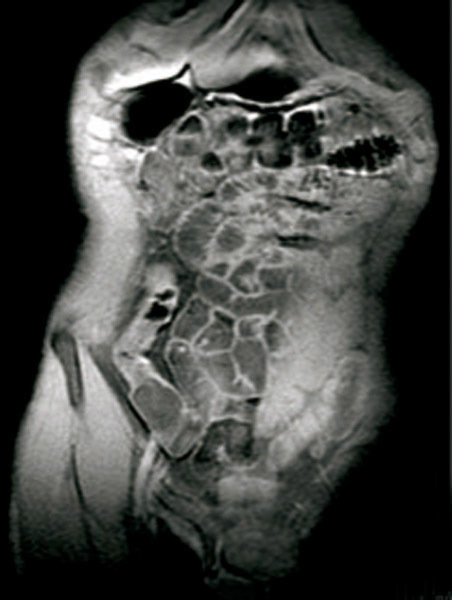

Entéro-IRM. Prise de contraste de la dernière anse iléale qui apparaît en hyper-signal T1 avant injection de gadolinium.